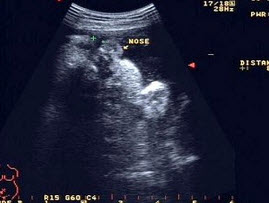

272、单项选择题

图为胎儿鼻唇区显像,“+”处标出的为()

A.鼻唇沟

B.伪像

C.右侧鼻孔

D.唇裂

E.以上都不是